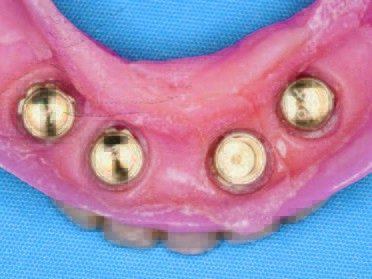

Die ATLANTIS Conus-Abutments, die zugleich als industriell gefräste Primärteile dienen sollten, sowie der zugehörige Einbringschlüssel wurden versandt. Die vier Conus-Abutments wurden unter Zuhilfenahme des Einbringschlüssels inseriert (Abb. 18). Es zeigte sich eine ausgezeichnete Parallelität. Danach wurden die Abutments implantatspezifisch (Astra Tech OsseoSpeed Abb. 14: Die vier verschiedenen Implantate in situ mit ihren jeweiligen Verschlusskappen. Abb. 15: Gingiva oder Sulkusformer. Abb. 16: Gingiva- oder Sulkusformer in situ. EV mit 25 Ncm, Straumann mit 35 Ncm, ANKYLOS mit 15 Ncm, Xive mit 24 Ncm) definitiv angezogen (Abb. 19). Abschließend erfolgte eine abschließende radiologische Kontrolle (Abb. 20). Die ANKYLOS Konuskappe Degulor für SynCone 5° wurden dem Patienten mitgegeben. Der überweisende Zahnarzt war in die Planung und Gestaltung der Endversorgung von Anfang an mit Abteilungsleieinbezogen. Seitens der Autoren wurde die Einpolymerisierung der Konuskappen (Abb. 20) in die vorhandene Prothese allein aus wirtschaftlichen Erwägungen angeraten.